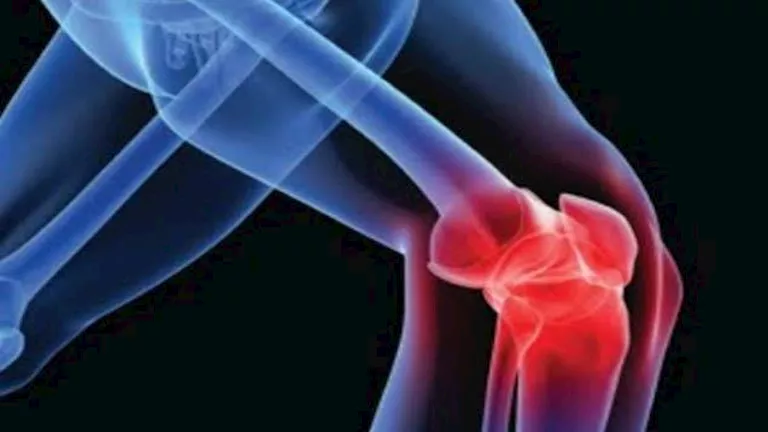

كشفت دراسة حديثة أجرتها جامعة تولين الأمريكية أن الإفراط في تناول الأطعمة فائقة المعالجة يضر بصحة العظام، هذه الأطعمة تؤدي إلى انخفاض كثافة المعادن في العظام وتزيد بشكل ملحوظ من خطر الكسور، وفقا لموقع “eurekalert”.

شملت الدراسة أكثر من 160 ألف مشارك على مدى 12 عاما، ووجد الباحثون أن زيادة 3.7 وجبات يوميا من هذه الأطعمة تعادل وجبة سريعة واحدة، وتؤدي إلى ارتفاع خطر كسور الورك بنسبة 10.5%.

كما أظهرت الدراسة انخفاضا في كثافة العظام خاصة في عظم الفخذ العلوي والعمود الفقري القطني.

أظهرت النتائج أن الأشخاص تحت سن 65 عاما، ومن يعانون من نقص الوزن، هم الأكثر تأثرا بالأطعمة فائقة المعالجة، كما أن الوظائف الهضمية الأقوى للشباب تؤدي إلى امتصاص أكبر للمكونات الضارة، بينما يشكل انخفاض مؤشر كتلة الجسم عاملاً إضافياً يزيد تأثير هذه الأطعمة على العظام.

تشير الدراسات السابقة إلى أن هذه الأطعمة تزيد خطر الإصابة بهشاشة العظام، ففي عام 2024، ارتبطت بالأطعمة المصنعة بهشاشة العظام، بينما أظهرت دراسة عام 2016 أن الأطفال المولودين لأمهات يعيشن قرب مطاعم الوجبات السريعة لديهم انخفاض في المحتوى المعدني لعظامهم.